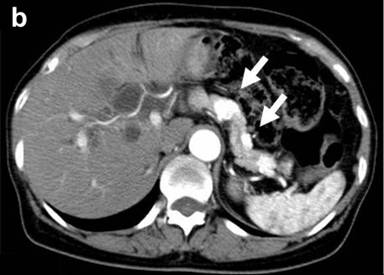

A 67-year-old female was referred to our hospital, complaining of jaundice, appetite loss and 3 kg of body weight loss over one month. She had undergone a thyroidectomy for a thyroid adenoma and a right oophorectomy for an ovarian tumor at 41 years of age and a right nephrectomy for renal cell carcinoma at 47 years of age. Laboratory data demonstrated mild liver dysfunction due to obstructive jaundice without elevation of plasma CEA and CA 19-9 levels. Computed tomography (CT) demonstrated a remarkably enhanced tumor measuring 55x40 mm in diameter in the head, two tumors measuring 2.0 and 1.8 cm in the body, and two tumors measuring 1.2 and 1.0 cm in the tail with a similar enhancing effect (Figure 1abc). CT angiography did not demonstrate any abnormalities of the arteries and the dorsal pancreatic artery branching from the origin of the splenic artery (Figure 1d). Magnetic resonance imaging demonstrated obstruction on the intrapancreatic bile duct due to a pancreatic head tumor and a slight dilatation of the main pancreatic duct in the body and tail of the pancreas. Fluorine-18 fluorodeoxyglucose positron emission tomography detected an elevated uptake in the isolated multifocal metastatic pancreatic tumors without any extrapancreatic uptake. A biliary drainage tube was inserted endoscopically. Cytology of the pancreatic juice was negative. The patient was diagnosed with isolated pancreatic metastases from renal cell carcinoma. The huge tumor located in the head was resected by a pancreaticoduodenectomy and the four tumors located in the body and in the tail of the pancreas were resected by a distal pancreatectomy, preserving the cervical portion. Intraoperative confirmation of arterial perfusion in the middle segment was necessary. In other cases, a total pancreatectomy should be done. Enucleation was not considered due to the risk of main pancreatic duct injury.

Figure 1. Preoperative computed tomography. Pancreatic metastatic tumors were detected as being demarcated enhanced tumors in the tail (a.) and body (b.) of the pancreas. A very large tumor occupied the entire head of the pancreas (c.). The common bile duct was compressed by the tumor located in the head of the pancreas (d.). |